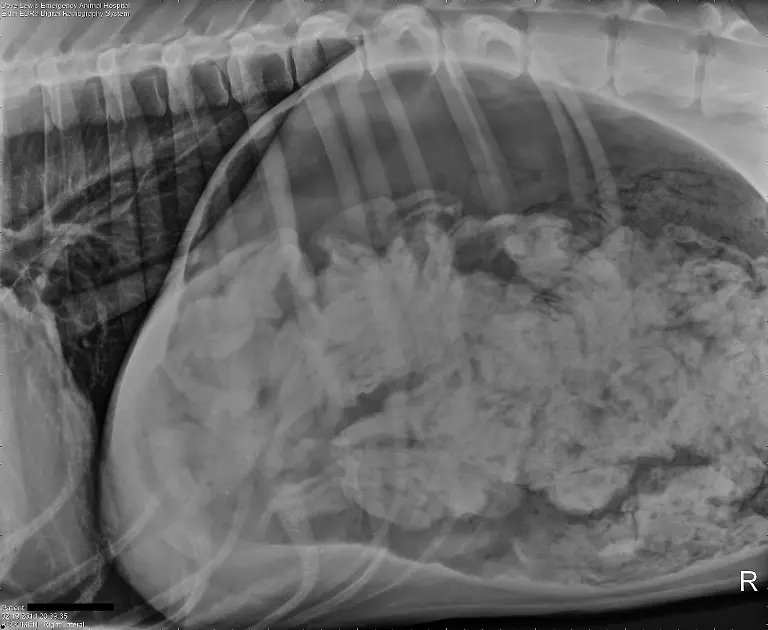

Socken, Kieselsteine, Außerirdische - Röntgenbilder von Mägen US-amerikanischer Haustiere zeigen die skurrilsten Gegenstände. Eine Zeitschrift zeichnet jedes Jahr die außergewöhnlichsten Aufnahmen aus.